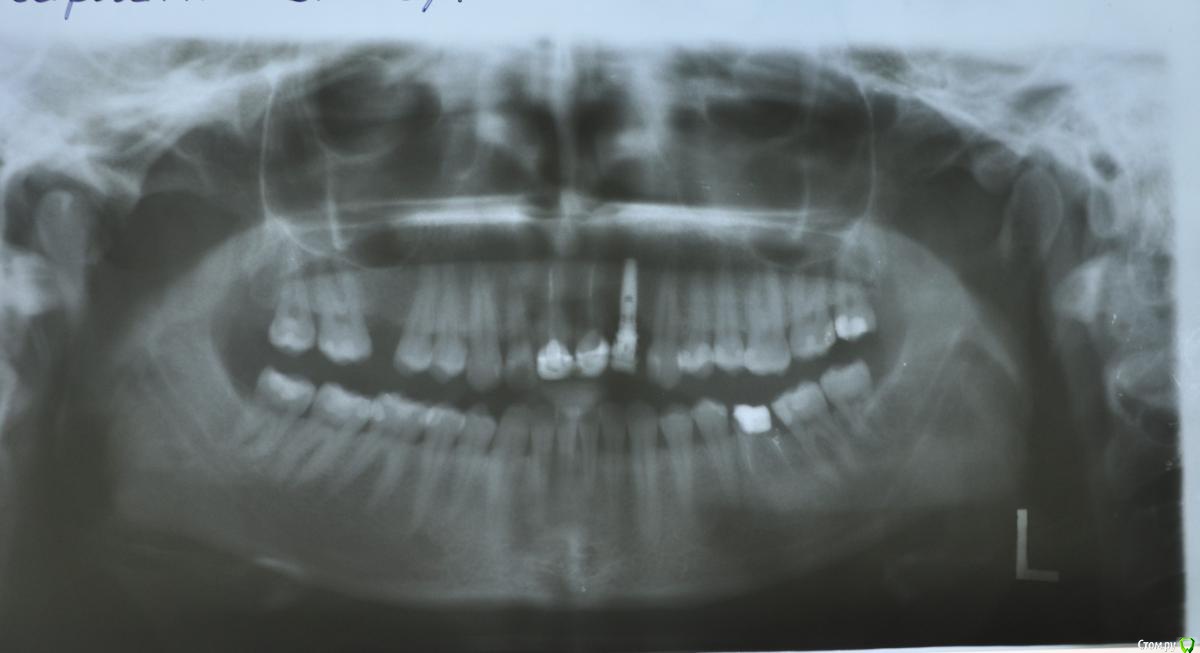

Лисица Опубликовано 25 июля, 2015 Поделиться Опубликовано 25 июля, 2015 (изменено) Начала ныть верхняя правая семерка, пошла к врачу - обнаружился глубокий скрытый прикорневой кариес. Совсем его не видно было После беременности и ГВ понавылазило.Вскрыв, врач сказала, что надо удалять нерв и пломбировать каналы. В процессе чистки все было хорошо, боли не было, как вдруг почувствовала резкий болезненный укол и потом стало ныть. Обратила внимание доктора на это, она добавила еще обезболивающего, но боль не прошла. Через некоторое время с штифтами (или как они называются) в каналах пошли на снимок. Сразу после вставания с кресла накатила пульсирующая сильная боль. (С начала лечения прошло около 30 минут.) После снимка и возвращения в кресло врач удалила эти иглы, еще почистила и - попросила зажать нос и дуть в него несколько раз. Оп-па. Вот тут я и поняла, что это была за боль После того как я смогла закрыть рот и говорить, спросила про перфорацию. Она сказала, что у вас, мол, такое строение челюсти, что ж я могу поделать. При вопросе об опасности такой ситуации замялась, потом сказала, что разве только при цементировании если попадет материал, но мы эту ситуацию отследим и не допустим. Сейчас она положила лекарство, временную гуттаперчевую пломбу и временным цементом замазано. Прошло около 4 часов после процедуры, верхняя челюсть ноет и периодически резко "колет". При наклоне головы влево по задней стенке глотки стекает жидкость с резким "медицинским" вкусом. Меня интересует, чем это мне может грозить в настоящий момент (до постоянной пломбировки), насколько часты осложнения? Какова вероятность, что придется удалять зуб? Или это частая ситуация и все заживет само? Можно ли было избежать такой ситуации и права ли врач, что раз у меня такое строение челюсти, то такая перфорация при чистке каналов неизбежна? Еще при моих вопросах, что делать если все же при цементировании загонят слишком глубоко материал и он вылезет в пазуху, как этого избежать, она сказала, что сделает снимок и если гуттаперчевый материал будет заходить слишком далеко, то она вытащит и поставит потолще, чтобы он не доходил до пазухи. Это действительно решение проблемы? Мне не давали никаких рекомендаций, может, стоит пропить антибиотики? Или лучше сперва посмотреть динамику? А то год назад удаляли зуб (правда, после воспаления и нагноения), неделю не заживала лунка и сильно болела, а быстро заживать стала только после курса Сумамеда. Прикрепляю на всякий случай ортопантомограмму старую 2013 года, может пригодится для оценки каналов. Извините за столько вопросов, но в таких больных во всех смыслах проблемах лучше перебдеть, чем недобдеть... PS Хм, похоже снимок не прикрепился. Еще раз пробую. Изменено 25 июля, 2015 пользователем Лисица Ссылка на комментарий

Лисица Опубликовано 25 июля, 2015 Автор Поделиться Опубликовано 25 июля, 2015 Извините, первый раз снимок почему-то не прикрепился. Отредактировала первое сообщение, добавив ортопантомограмму, правда, старую. Прицельный не делали вообще перед лечением. Снимка, сделанного во время лечения, увы, не имею, до моего затуманенного болью мозга стало что-то доходить уже по пути домой. А врач следующий раз работает только в среду, когда назначено окончание процедуры лечения. А в общих чертах хотя бы можно перспективы обрисовать? А то я сильно нервничаю Ссылка на комментарий

Лисица Опубликовано 27 июля, 2015 Автор Поделиться Опубликовано 27 июля, 2015 St., большое спасибо за ответ! Моя врач планировала закрыть его в среду (зная о том, что пазуха проткнута). Если запломбировать, пока воспаление есть, какие могут быть проблемы? И еще она сказала, что нащупала 4-й тонкий канал, но не было времени его прочистить, так что она оставила как есть до среды. Сказала, что почистит и сразу же закроет. Судя по КТ, корня 3, значит в одном из них 2 канала? В 3D похоже, что корни с медиальной стороны сросшиеся какие-то... и на небном тоже борозда. Ссылка на комментарий